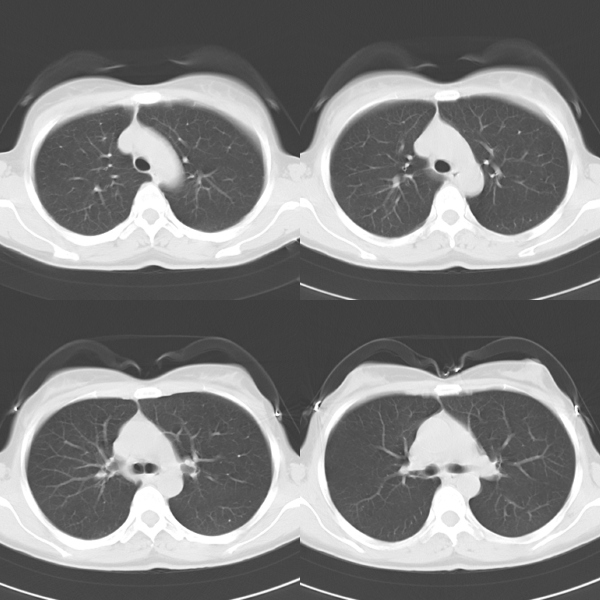

标题: CT19623:F40y,肋骨改变。

40岁女性,双侧胸部疼痛,以左侧为明显1+年。余无明显异常。

左侧肋骨单发膨胀性病变,皮质连续,病史较长,首先考虑良性病变:骨纤可能性大。